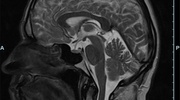

Kopf/Hals

• akute Schlaganfalldiagnostik und chronische Durchblutungsstörungen

• entzündliche Prozesse des Gehirns oder der Gesichtsweichteile

• Tumore

• Abklärung Schwindel, zentrale Sehstörung, Kopfschmerz

• Metastasenverdacht

• Multiple Sklerose

• Abklärung Hirnnerven, Schädelbasis inkl. Hypophyse

• Abklärung Kleinhirn, Hirnstamm, Halsmark

• intrakranielle Gefäße (Abklärung Verschluss, Stenose, Aneurysma)

• Halsgefäße zur Therapieplanung (z.B. Stent, Operation)